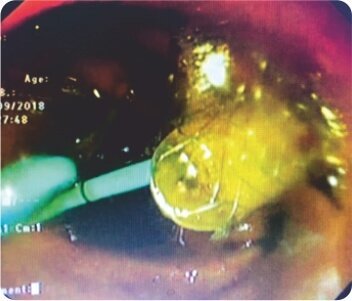

EUS guided puncture of IHBRD in the second segment of liver was done from stomach and after the cholangiogram, the tract was dilated sequentially using cystotomes till 10F and a 60×10 mm fully covered biliary metal stent was deployed connecting the stomach and the second segment of liver. A 7F 7cm double pigtail plastic stent was deployed within the metal stent to prevent its displacement. There were no periprocedural complications and the patient underwent chemotherapy after normalization of bilirubin. During follow-up 3 months after the procedure, the patient’s LFT remained normal.

FCSEMS placemen

FCSEMS with aplastic stent within